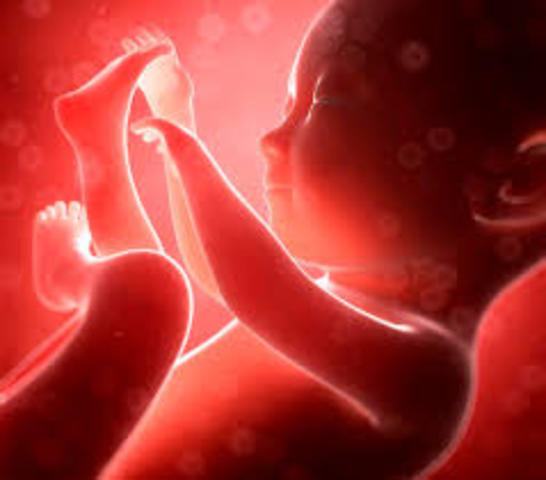

• semana 20 de embarazo

semana 20 de embarazo

Ya son 20 semanas de embarazo, ¡has llegado a la mitad del embarazo! Solemos hablar de 40 semanas de embarazo a partir de la última menstruación. Sin embargo, la duración puede variar de 37 a 42 semanas. En la semana 20 de embarazo el bebé mide aproximadamente 16 cm largo y pesa cerca de 255 gramos pero, como sabrás, al bebé le falta mucho por crecer.